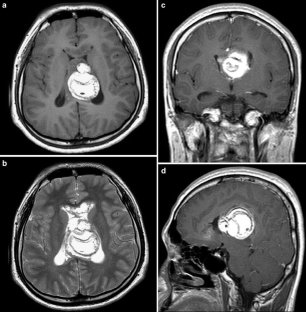

This case involves an 18-year-old man who presented with abnormal behavior, impairment in recent memory, and emotional change. Five years ago, he received five cycles of chemotherapy using cisplatin and ectoposide and 24G of local radiotherapy for clinical diagnosis of suprasellar germinoma in another hospital. The tumor was then completely resolute. Magnetic resonance imaging in our hospital revealed a large fatty mass located primarily in the septum pellucidum and some portions of the corpus callosum; a heterogeneous enhancing tumor was observed in the surrounding area. The second tumor was completely removed. The histological diagnosis was mixed GCTs containing the component of a germinoma and a mature teratoma.